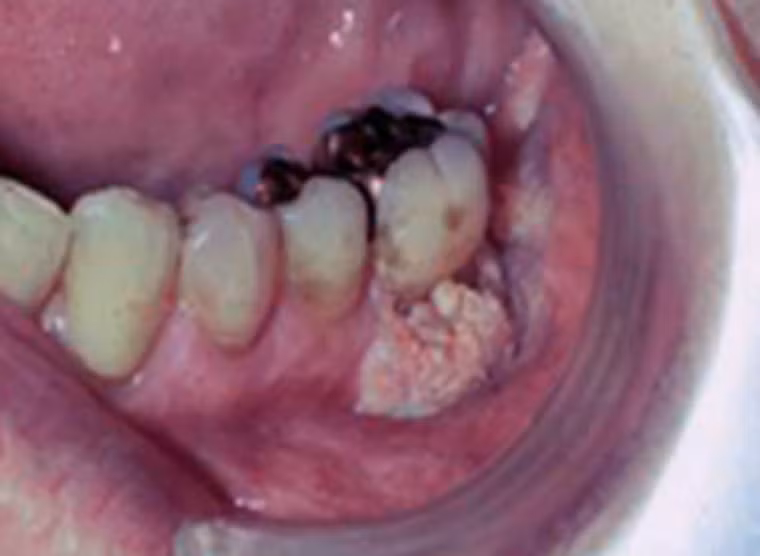

Còn đây là khoang miệng người phụ nữ 31 tuổi vừa được chẩn đoán mắc ung thư. Răng cùng một số mô xung quanh chuyển sang màu đen và có dấu hiệu di căn khá mạnh sang các tế bào khác.